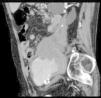

The patient was an 86-year-old man who was taking 2 medications for hypertension. He had a history of several months of low back pain that radiated to right thigh, for which symptomatic treatment provided partial relief. His rheumatologist had ordered thoracolumbar magnetic resonance imaging (MRI), but it was not performed because, prior to the scheduled date, the patient went to the emergency department with an increase in the intensity of the pain. Laboratory analyses showed a hemoglobin level of 8.4g/dL, lactate dehydrogenase of 318U/L, creatinine of 1.29mg/dL, C-reactive protein of 6.16mg/dL, erythrocyte sediment rate of 24mm/h and mild hypoproteinemia. There was no evidence of hemodynamic instability. He underwent abdominopelvic computed tomography (CT) with intravenous contrast, which revealed isolated bilateral iliac aneurysms>6cm (Fig. 1) with contained rupture of the aneurysm on the right (Fig. 2), which displaced the psoas muscle (Fig. 3) and perforated the ipsilateral iliac bone (Fig. 4). The patient underwent aortobifemoral bypass but, unfortunately, he died during the postoperative period.

Isolated iliac aneurysms, without an associated aortic aneurysm, are rare.1 They are relatively difficult to identify, as up to 40% of them may present with rupture.2 The incidence rate of extraspinal causes of sciatica is low.3 Likewise, chronic rupture of an aneurysm constitutes a peculiar entity. All these circumstances coming together result, in most cases, in an erroneous or late diagnosis.4 It is usually a dorsolateral rupture toward the anterior insertions of the psoas muscle, which contains the hematoma, avoiding massive extravasation, but not the infiltration of the roots of the lumbosacral plexus. This produces chronic low back pain that radiates to the lower limb,5 this being the most common presentation.6 The diagnosis can be based on abdominal CT,7 and lumbar MRI (parasagittal slices).7,8 The aneurysm may undergo secondary acute rupture at any time.4 This case serves to remind us, in our routine practice, that an aneurysm may be involved in the symptoms of sciatica.9